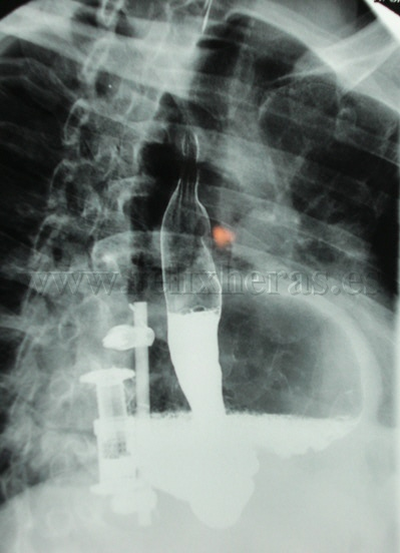

Hernia diafragmática traumática